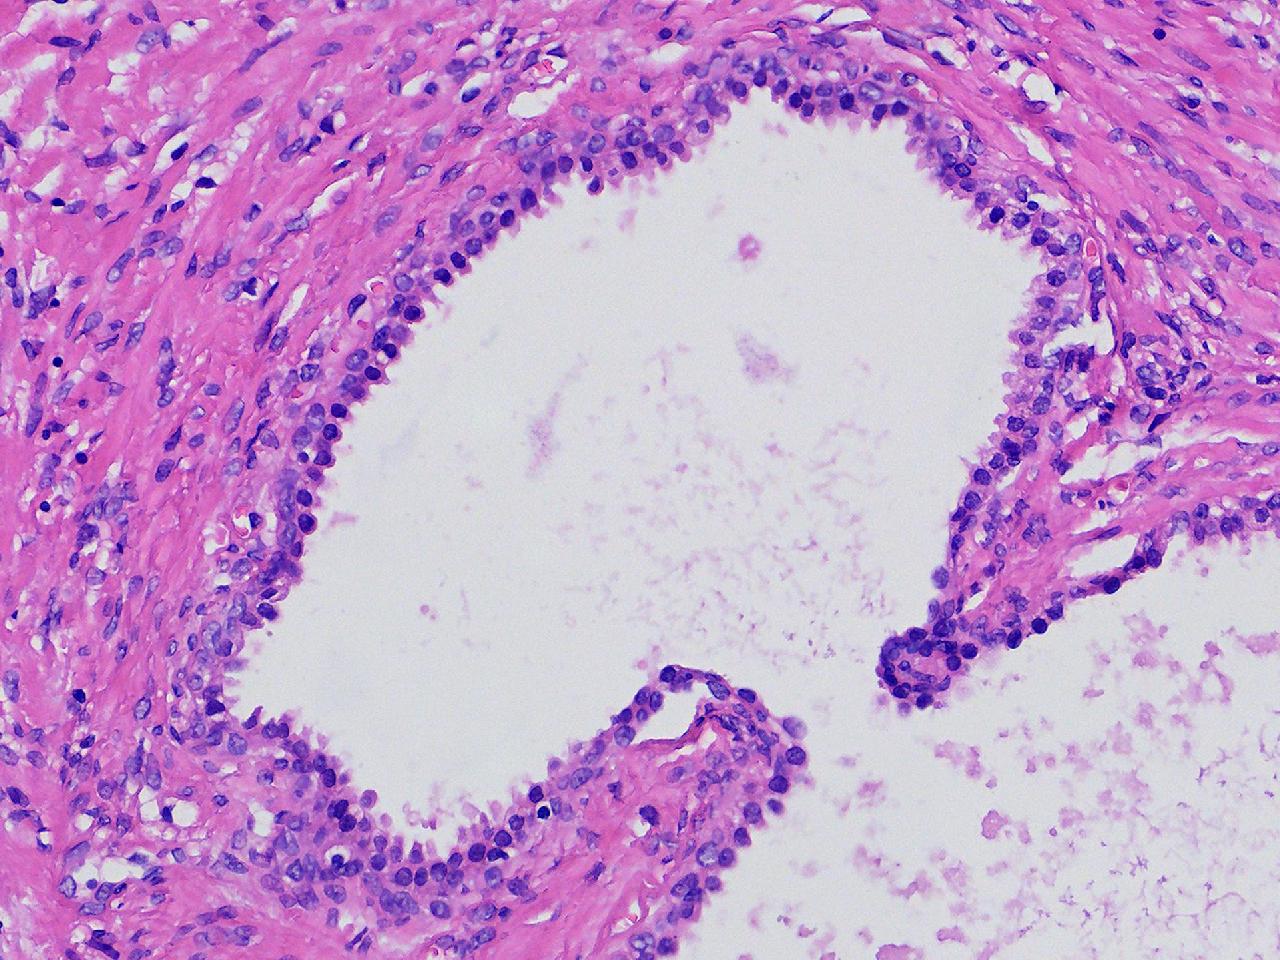

良性前列腺增生?

男,68岁,前列腺电切标本。

前列腺电切标本

灰粉色条索状软组织多块,5X4X3厘米。

前列腺增生。

BPH.